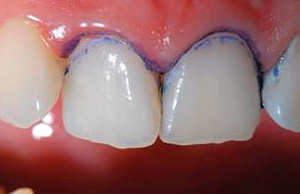

L'indicatore di carie si è dimostrato molto valido per educare i giovani medici e studenti, nonché per dimostrare le aree interessate al paziente stesso. Spesso viene anche utilizzato per monitorare le condizioni delle aree di smalto vicino a corone e otturazioni (aiuta a violare l'adattamento marginale di otturazioni, crepe, posizionamento improprio), nelle fessure, dove è molto difficile notare lo sviluppo della carie nelle prime fasi.